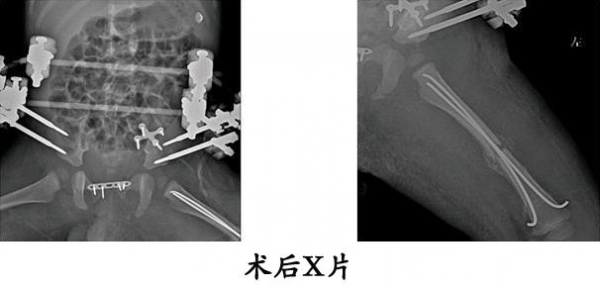

13.严某某,女,4岁,高处坠落伤(股骨颈、股骨干骨折),术后恢复颈干角、前倾角。